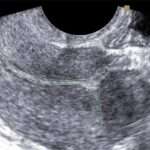

Рубець на матці після кесаревого розтину

Зміст:Норма і патологія рубцяВід чого буває неповноцінний рубецьУскладнення неповноцінного рубцяКлінічні рекомендаціїСпособи лікуванняВедення вагітності при наявності рубцяПологи після КРКесарів розтин деколи буває єдиним способом розродження, але після такого втручання незмінно залишається рубець на матці.